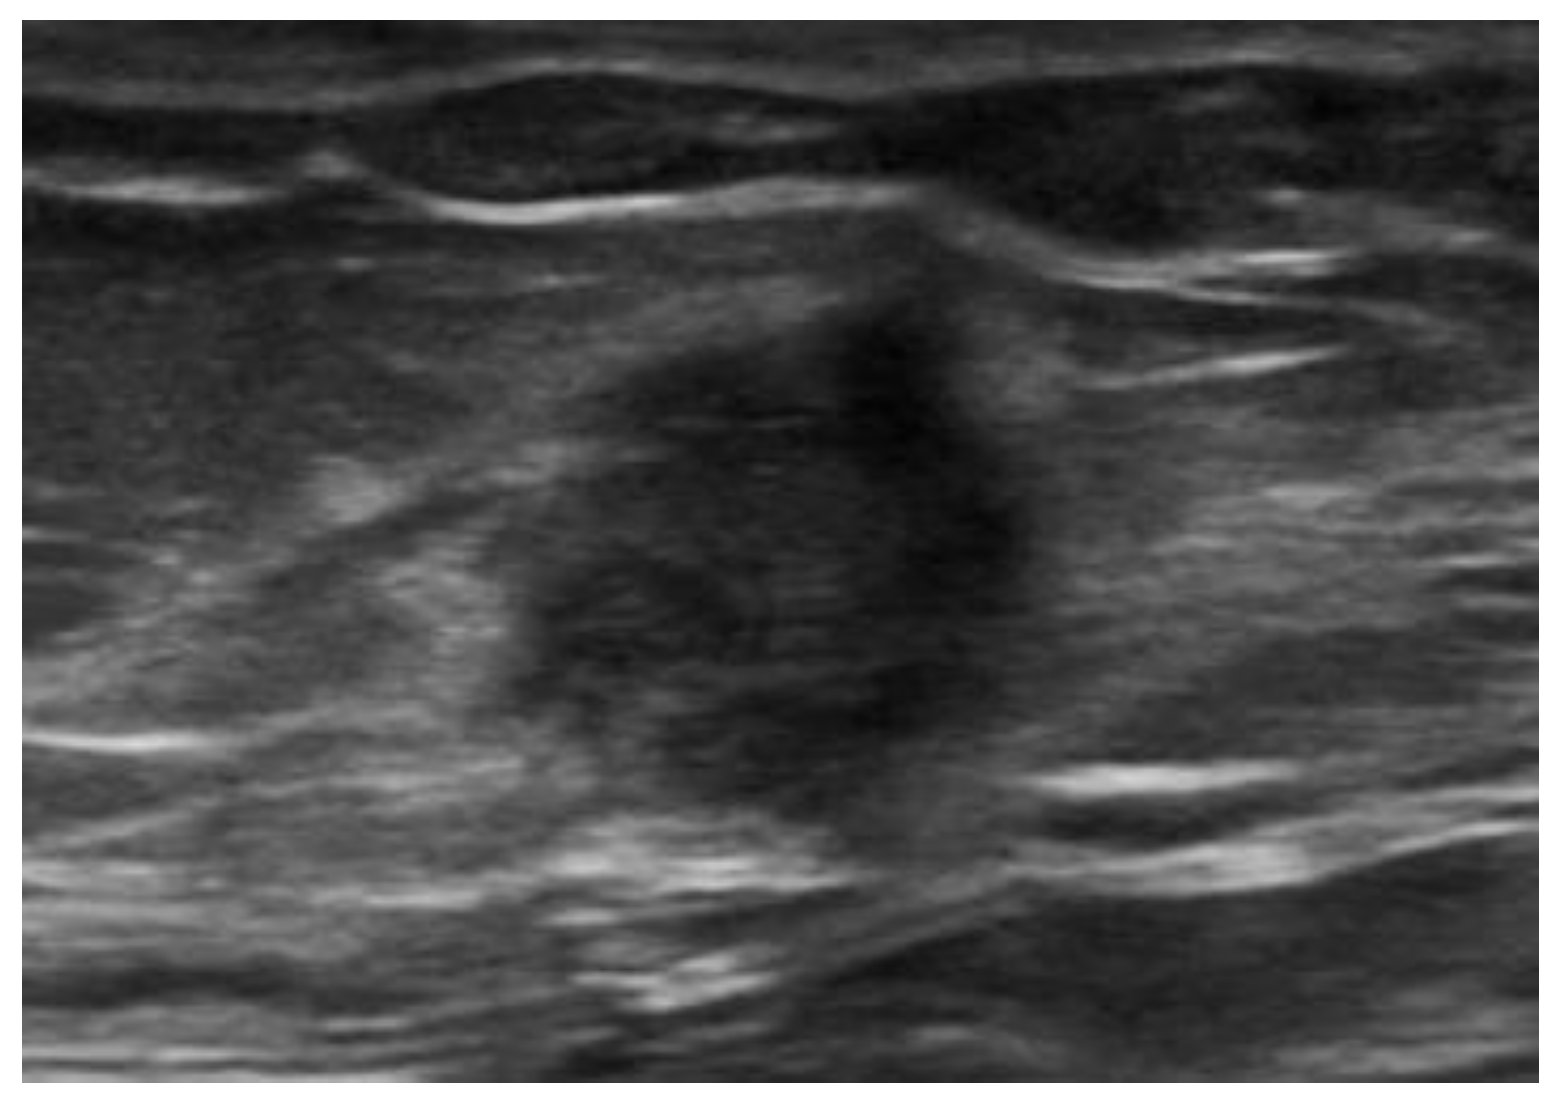

5.3. Subcutaneous Drugs